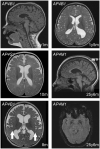

Bi-allelic loss-of-function variants in genes that encode subunits of the adaptor protein complex 4 (AP-4) lead to prototypical yet poorly understood forms of childhood-onset and complex hereditary spastic paraplegia: SPG47 (AP4B1), SPG50 (AP4M1), SPG51 (AP4E1) and SPG52 (AP4S1). Here, we report a detailed cross-sectional analysis of clinical, imaging and molecular data of 156 patients from 101 families. Enrolled patients were of diverse ethnic backgrounds and covered a wide age range (1.0-49.3 years). While the mean age at symptom onset was 0.8 ± 0.6 years [standard deviation (SD), range 0.2-5.0], the mean age at diagnosis was 10.2 ± 8.5 years (SD, range 0.1-46.3). We define a set of core features: early-onset developmental delay with delayed motor milestones and significant speech delay (50% non-verbal); intellectual disability in the moderate to severe range; mild hypotonia in infancy followed by spastic diplegia (mean age: 8.4 ± 5.1 years, SD) and later tetraplegia (mean age: 16.1 ± 9.8 years, SD); postnatal microcephaly (83%); foot deformities (69%); and epilepsy (66%) that is intractable in a subset. At last follow-up, 36% ambulated with assistance (mean age: 8.9 ± 6.4 years, SD) and 54% were wheelchair-dependent (mean age: 13.4 ± 9.8 years, SD). Episodes of stereotypic laughing, possibly consistent with a pseudobulbar affect, were found in 56% of patients. Key features on neuroimaging include a thin corpus callosum (90%), ventriculomegaly (65%) often with colpocephaly, and periventricular white-matter signal abnormalities (68%). Iron deposition and polymicrogyria were found in a subset of patients. AP4B1-associated SPG47 and AP4M1-associated SPG50 accounted for the majority of cases. About two-thirds of patients were born to consanguineous parents, and 82% carried homozygous variants. Over 70 unique variants were present, the majority of which are frameshift or nonsense mutations. To track disease progression across the age spectrum, we defined the relationship between disease severity as measured by several rating scales and disease duration. We found that the presence of epilepsy, which manifested before the age of 3 years in the majority of patients, was associated with worse motor outcomes. Exploring genotype-phenotype correlations, we found that disease severity and major phenotypes were equally distributed among the four subtypes, establishing that SPG47, SPG50, SPG51 and SPG52 share a common phenotype, an 'AP-4 deficiency syndrome'. By delineating the core clinical, imaging, and molecular features of AP-4-associated hereditary spastic paraplegia across the age spectrum our results will facilitate early diagnosis, enable counselling and anticipatory guidance of affected families and help define endpoints for future interventional trials.